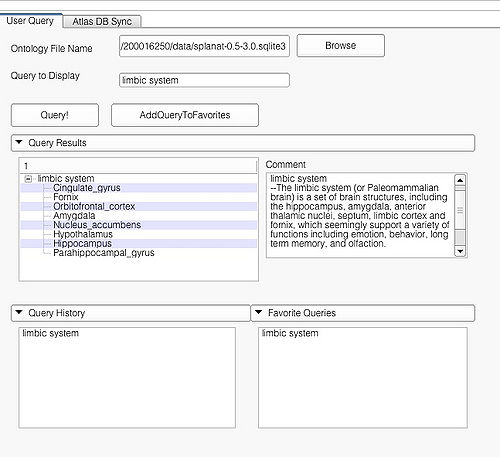

This page is useful for creating visualizations based on user typed queries. The user inputs consist of the Ontology File Name and Query To Display. The button Query fires a query and causes the module to start processing the user query for visualization. The button AddQueryToFavorites adds the last typed user query to the list of favorite queries. The favorite query list is shown in the bottom panel Favorite Queries. Additionally, the interface also shows a history of typed queries in the panel Query History.

The Query Results panel shows the result of a query, consisting of all the associated predicates and parts for the query. The Figure User Page GUI shows the result of a simple query "limbic system".Additionally, the interface also shows a Comment that contains any relevant textual information about the query obtained from the ontology. The user can refine a search by selecting from the query result. Optionally, the user can also select by clicking on any selection from the Query History or Favorite Queries panel to redo search and visualization. The interface supports the multiple selections to form complex queries. The visualization resulting by searching with the query "Limbic system" is shown below.

Simple query is a self-contained individual string that is matched in entirely with the ontology. An example of a simple query is "limbic system". The result of this query is shown above.